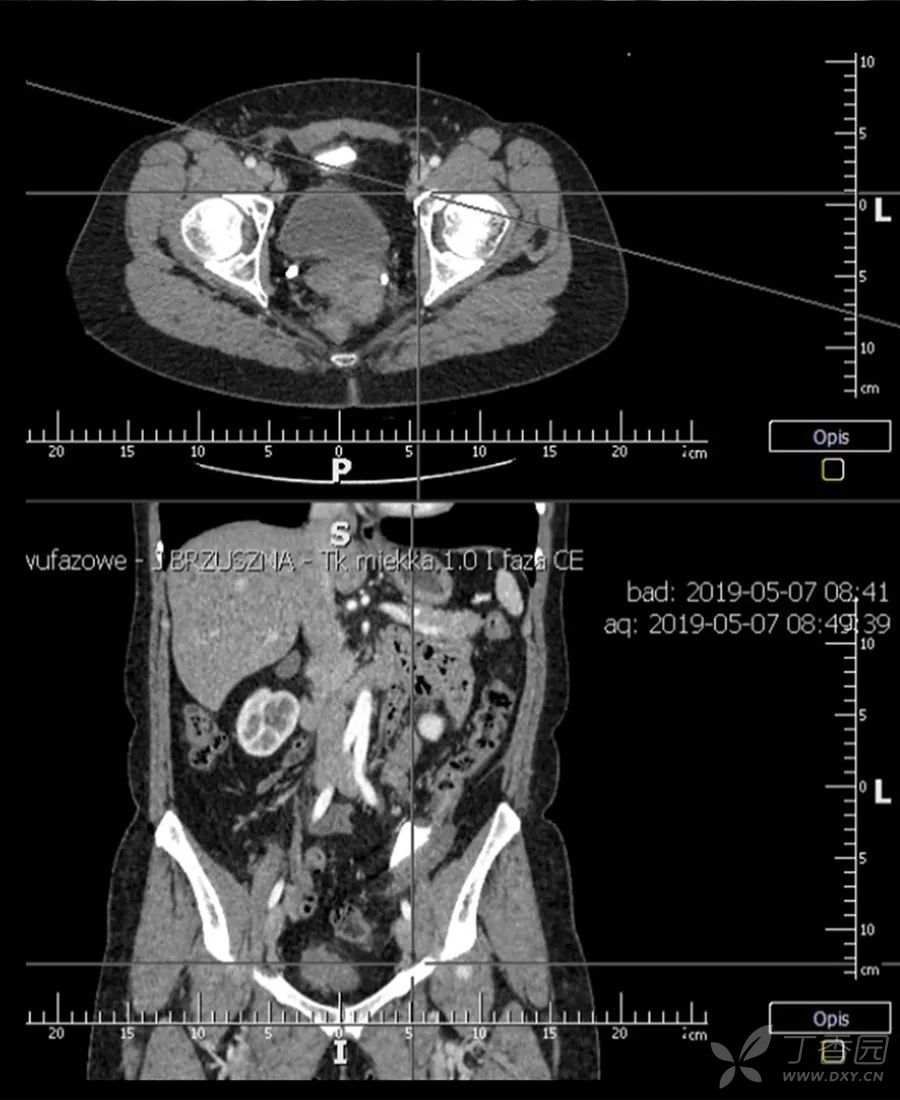

腹腔CT

在腹腔内发现一块19厘米长的玻璃碎片,在盆腔内呈环状。